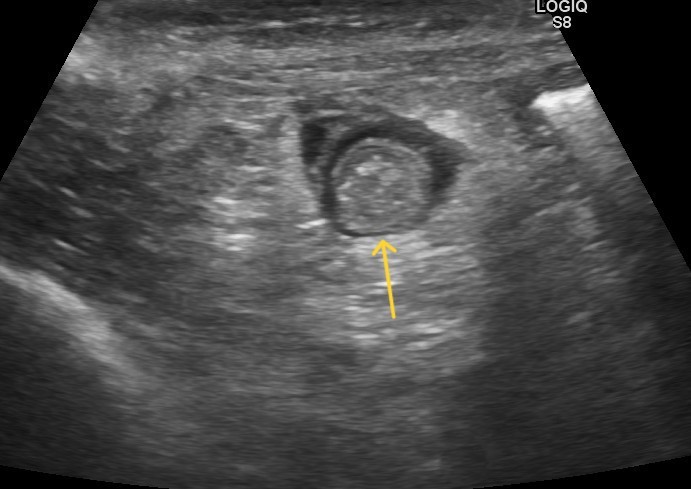

患者は西東京市在住17歳の雑種猫雌で食欲不振と嘔吐の主訴で来院しました。

腹部触診で腹腔内に腫瘤が確認されたため超音波検査を行ったところ、腸に腫瘍性病変を認めました。

写真上矢印 超音波検査で認められた腫瘍性病変